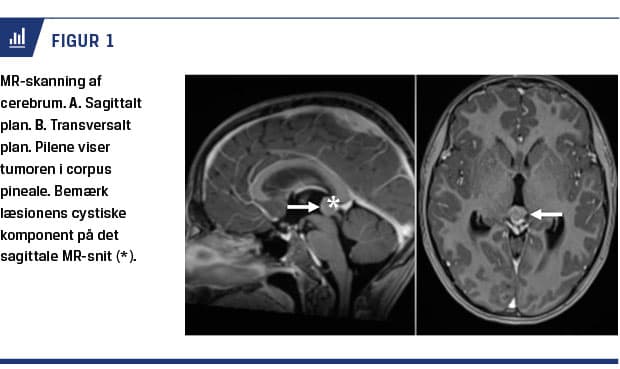

Der blev taget infektions- og stofskiftetal, og på mistanke om patologisk læsion i mesencefalon blev der udført MR-skanning af cerebrum. Blodprøver viste normale infektions- og stofskifteparametre og var i øvrigt negative for Borrelia burgdorferi ved serologisk undersøgelse. MR-skanning af cerebrum viste en tumor på 14 × 14 × 14 mm i corpus pineale. Tumoren indeholdt en cystisk komponent på 5-6 mm i diameter (Figur 1). Processen var prominerende ind i tredje ventrikel, men der var ingen radiografiske tegn på hydrocefalus. Processen var forenelig med et pinealom, hvorfor der blev udført lumbalpunktur og billedvejledt intrakranial biopsi fra læsionen. Sidstnævnte viste maligne tumorceller, der blev identificeret som germinale celler. Værdierne for alfaføtoprotein og humant choriongonadotropin i blodet såvel som spinalvæsken var normale. Der blev senere udført positronemissionstomografi/MR-skanning. Her blev der ikke påvist nogen tegn til tumorspredning.